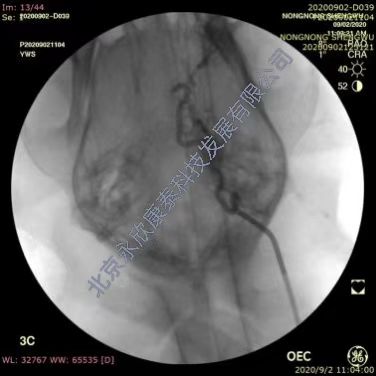

采用介入手术建立比格犬急性血栓性脑血管闭塞动物模型,分别于两侧腹股沟区备皮,消毒铺巾,穿刺右股动脉置入导管鞘,置入导丝,将5F单弯导管插至颈内动脉近端手推注显影剂确定血管走向,正侧位造影判断血管走行情况。用1mL注射器吸3~5条血栓条注入颈内动脉,造影证实颈内动脉颅内段末端栓塞,2h后造影复查血管的灌注情况,证实栓塞血管没有因血栓自溶复通,之后30min匀速脉滴注阿替普酶。溶栓治疗后1h,脑血管造影,判断血管复通情况,进行评分。